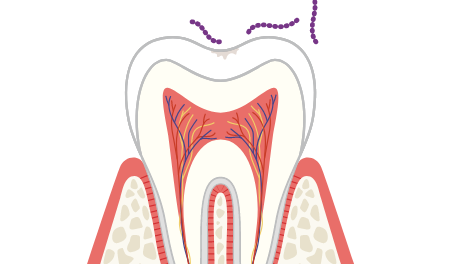

神経は感覚(温度差など)を司る組織で、歯の中にある歯髄(しずい)という場所に走っています。歯髄の中には歯や歯茎に栄養を送る血管も走っていますが、歯の神経を抜くとこの歯髄も取り除かなければいけません。

ですが、歯髄を取ってしまうと歯の感覚器官がなくなってしまい、栄養も行き届かなくなってしまいます。神経を取ってしまうと平均的に15年で歯が折れてしまうと言われていて、たとえむし歯がなくなっても長く健康な歯を保つことは難しいでしょう。